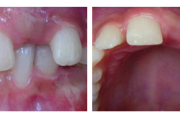

Lutipudelikaariese kahjustused

Lutipudelikaaries

Ravijärgne seis. Jäävhammas on täielikult lõikunud.